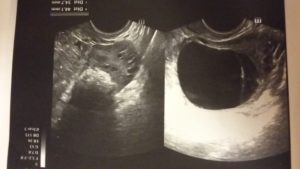

УЗИ снимок кисты желтого тела.

- УЗИ. В полости кисты отсутствуют кровеносные сосуды. Это является отличительной характеристикой лютеинового новообразования.

Уточнить диагноз позволяет УЗИ.